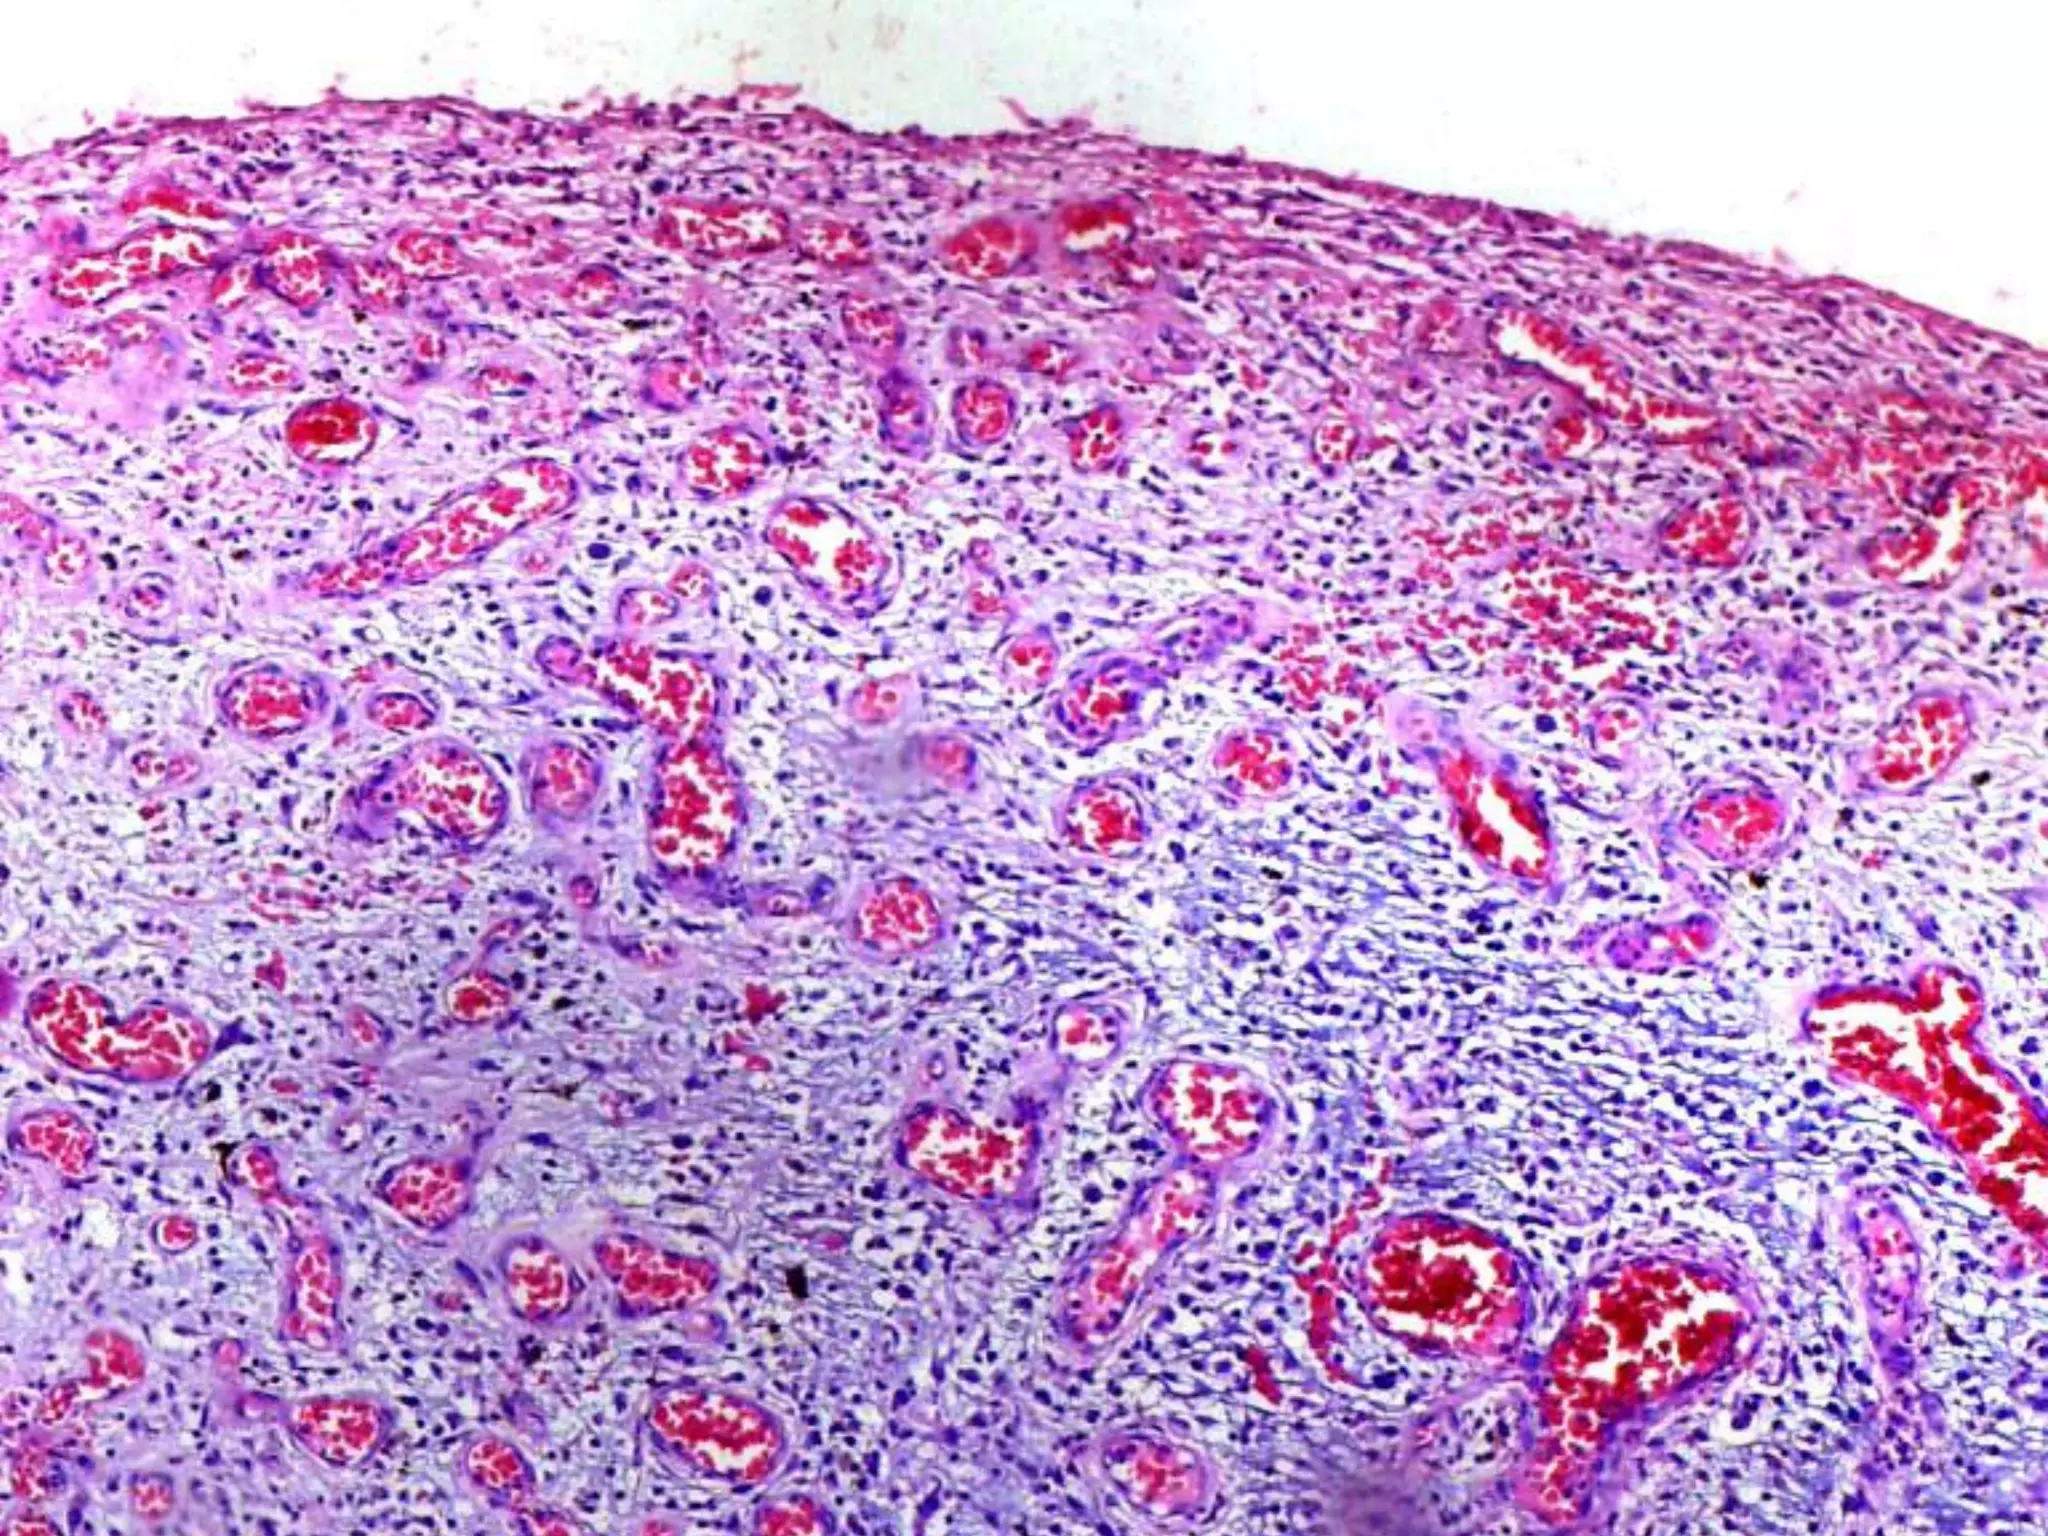

The document provides an overview of dermatopathology, including methods and techniques for skin biopsies such as shave, punch, and ellipse methods. It discusses key terms associated with dermatopathology, such as acantholysis and granulation tissue. Additionally, it references presentations by professionals in the field and essential dermatology resources.